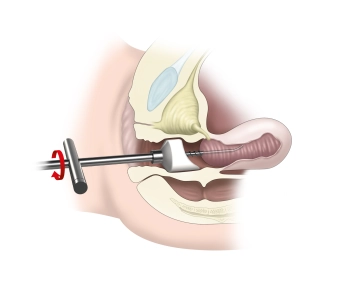

- Fixação de um adaptador cervical